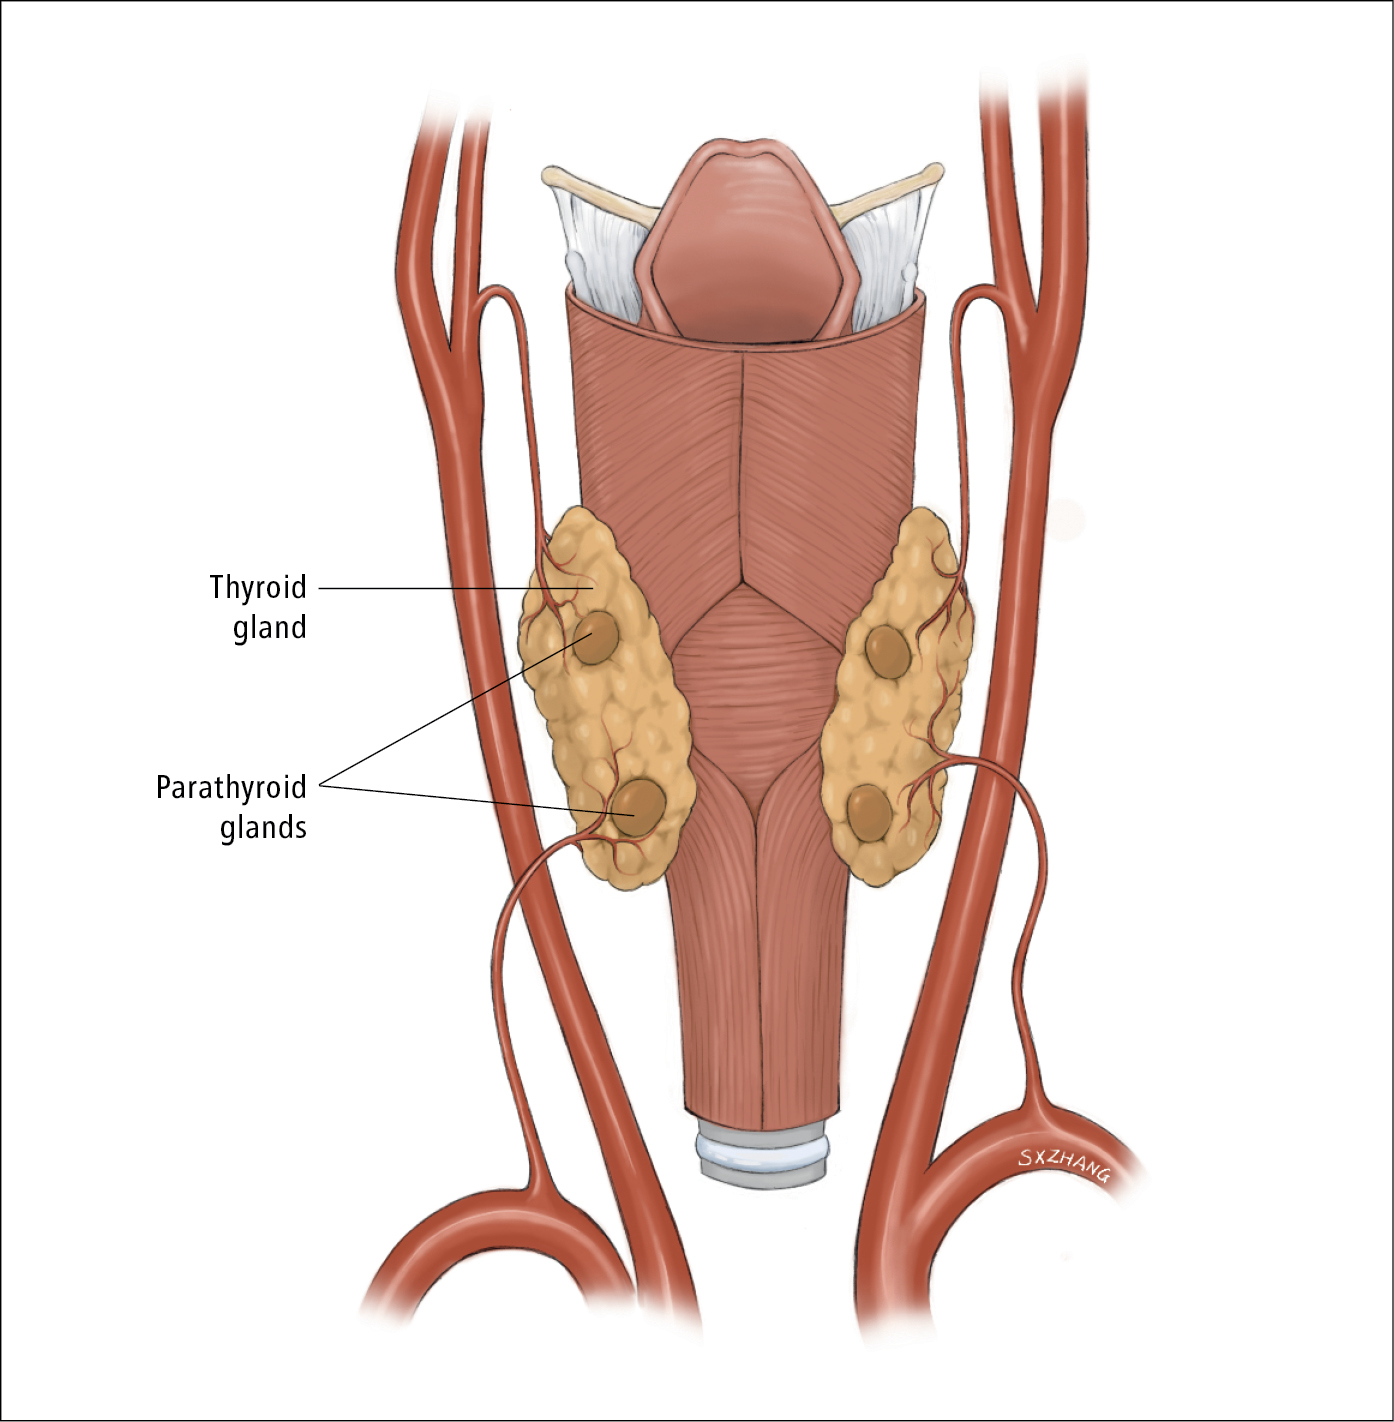

Иллюстрации и схемы по остеопорозу и паращитовидной железе